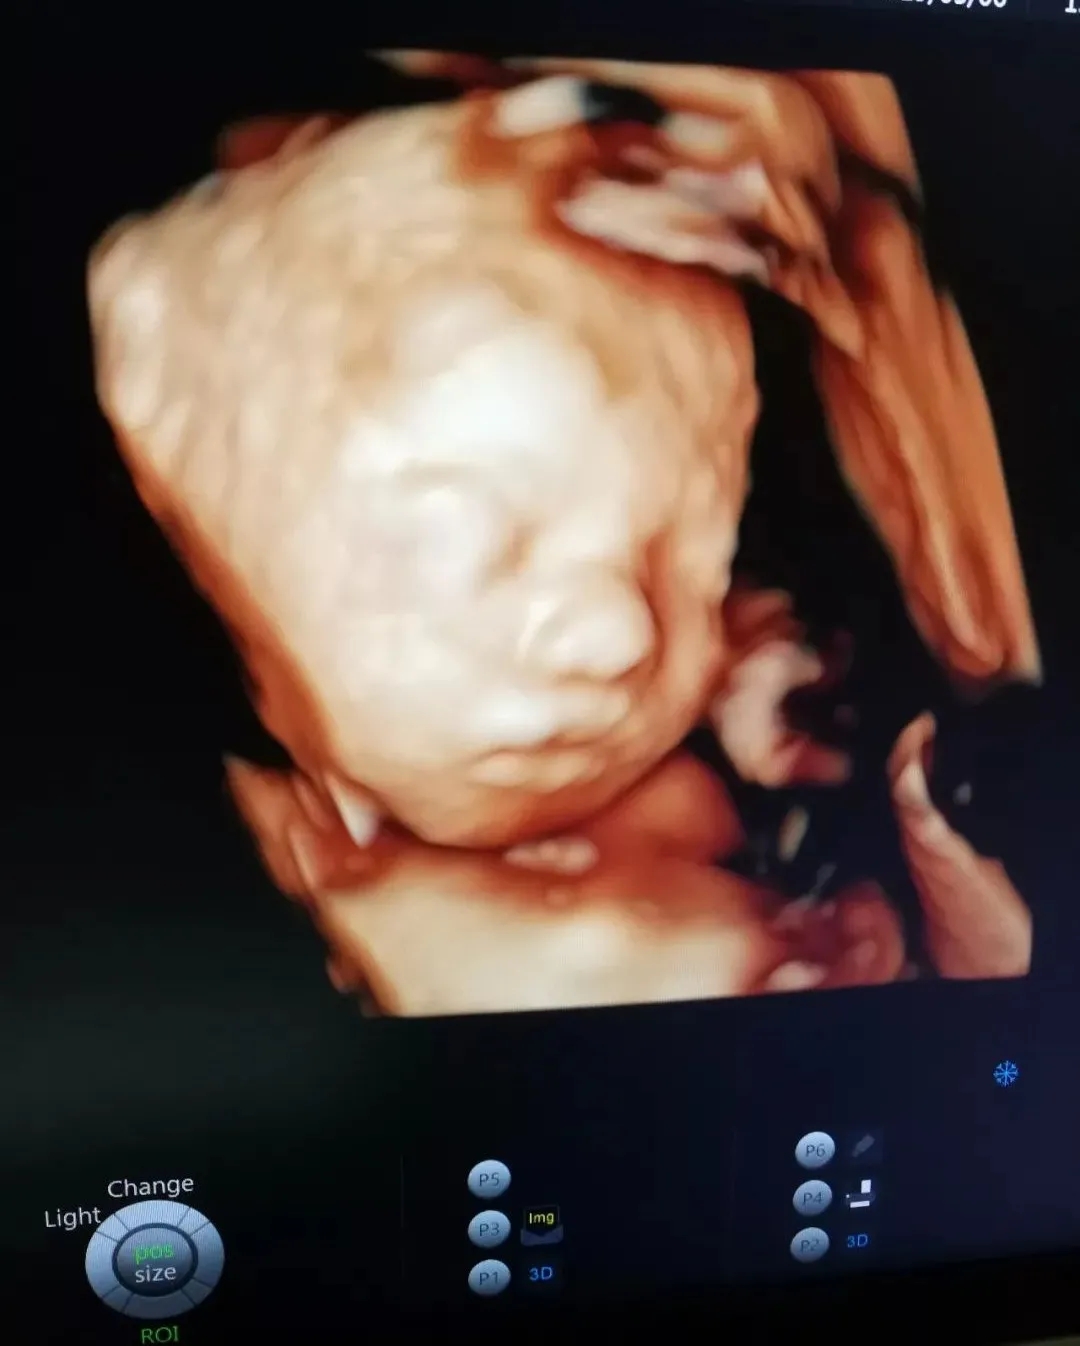

也许肚子里的宝宝

还不能说TA们对妈妈的爱

但通过美琳达的四维彩超画面中

TA们的活泼好动,萌萌的表情

已经说明了一切